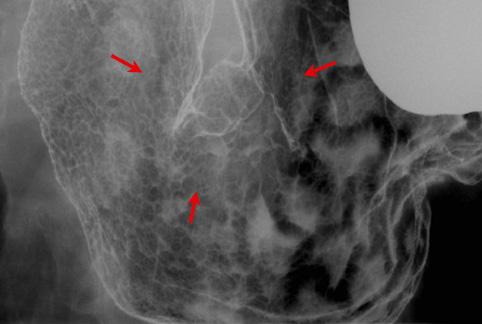

Criteria of Hist.ClassificationMalignant epithelial tumor/Adenocarcinoma

LocationStomach/Angle

Technique, MethodX-ray

Macroscopic TypesType 3 Ulcerated type with infiltration/

Size30 - 34

Depth of Tumor Invasionsubserosa (subadventitia)